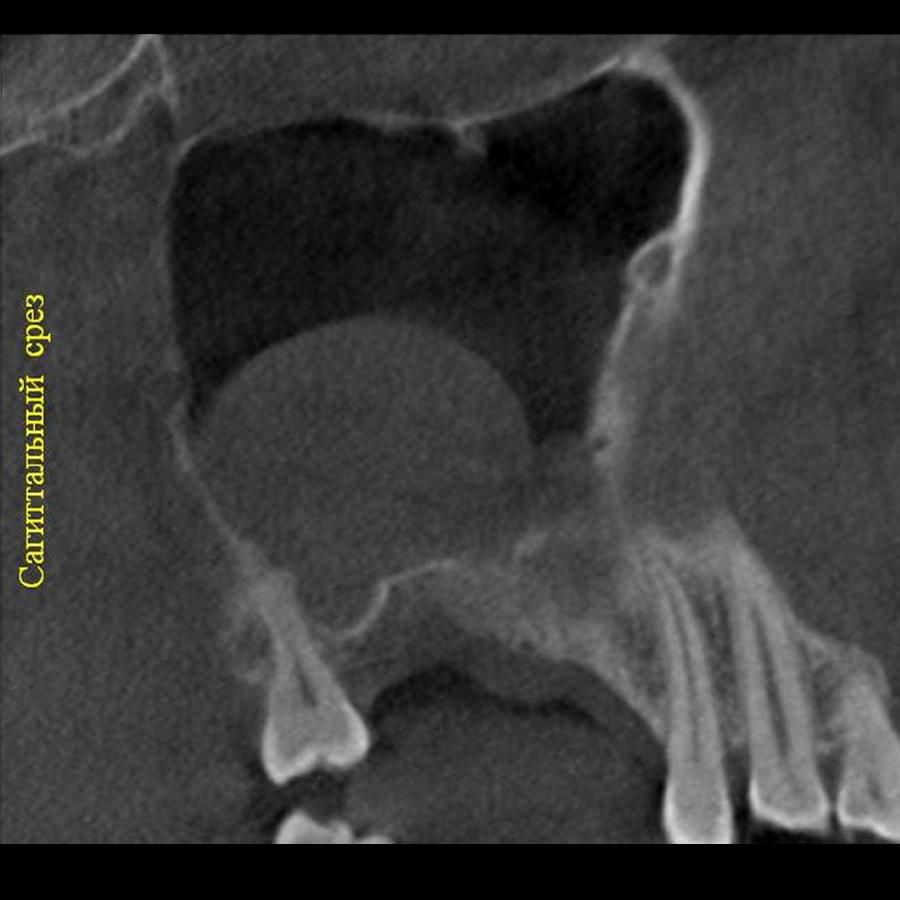

Комп'ютерна томографія

Щелепно-лицева діагностика

Мережа діагностичних центрів "МАЙРЕЙ ЛАБ" забезпечує точну та надійну діагностику

щелепно-лицевої ділянки з мінімальним ризиком для пацієнтів.

Ми використовуємо найсучасніше обладнання відомого виробника PLANMECA, що дозволяє отримувати високоякісні зображення за короткий час. Крім того, ми маємо власний сервер, на якому створюємо окрему скриньку для кожного лікаря, що забезпечує максимальну зручність та ефективність роботи.

3D цефалометричний аналіз є сучасною технологією, яка дозволяє отримувати точніші,

комплексніші та надійніші дані про зубну та скелетну структуру. Ця технологія може стати

великим кроком в перед для ортодонтів, які хочуть забезпечити найкраще можливе лікування

своїх пацієнтів.

Основні переваги 3D цефалометричного аналізу:

Точність: 3D цефалометричний аналіз забезпечує точніше визначення розмірів та відстаней між

зубами та кістковими структурами.

Комплексність: ця технологія дозволяє отримувати детальні дані про різні структури, такі як

кістка та м'язи, що дозволяє ортодонтам докладніше досліджувати деякі патології та планувати

лікування.

Надійність: 3D цефалометричний аналіз дозволяє отримувати надійніші результати, оскільки

виключає можливість помилок, пов'язаних зі спотворенням або перекриттям зображень.